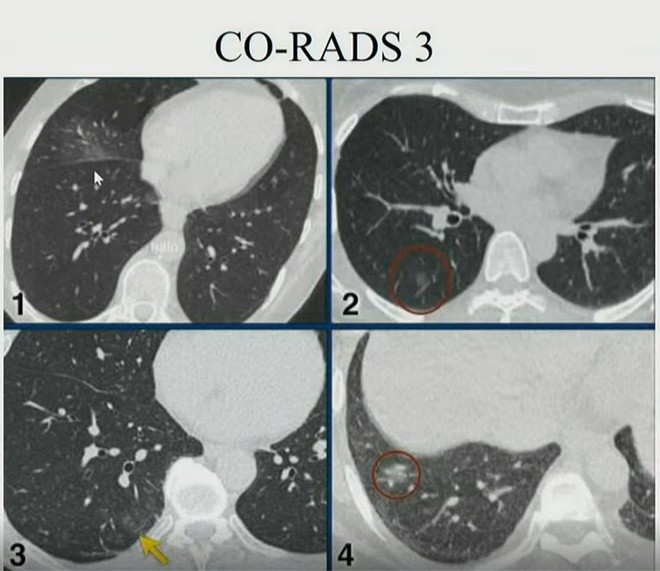

TS Lưu dẫn nghiên cứu của nhóm nhà khoa học Hà Lan cho thấy phân độ nghi ngờ Covid-19 dựa vào hình ảnh cắt lớp vi tính. Bác sĩ có thể kết luận người mắc Covid-19 khi chưa xét nghiệm rRT-PCR hoặc kết quả âm tính.

Hình ảnh chụp cắt lớp vi tính một số phân độ tổn thương phổi của người mắc Covid-19. - Ảnh: Bệnh viện Đại học Y Hà Nội.

6 phân độ (CO-RADS) nghi ngờ được xếp theo cấp độ tăng dần, trong đó, ở cấp độ 6, chắc chắn bệnh nhân nhiễm SARS-CoV-2. Cụ thể:

- CO-RADS 1: Phổi bình thường, không tổn thương.

- CO-RADS 2: Tổn thương nhưng ít và hình ảnh phổi đặc trưng cho những bệnh lý nhiễm trùng khác. Nguy cơ mắc Covid-19 thấp.

- CO-RADS3: Tổn thương có thể xảy ra ở bệnh nhân Covid-19 hoặc các bệnh phổ biến khác. Mức độ nghi ngờ trung bình.

- CO-RADS 4: Phổi có tổn thương kính mờ, dày tổ chức kẽ ở hai bên nhưng chưa đặc trưng ở bệnh nhân nhiễm SARS-CoV-2. Tuy nhiên, tỷ lệ lây nhiễm rất cao.

- CO-RADS 5: Nguy cơ rất cao. Xét nghiệm rRT-PCR lần một có thể âm tính nhưng gần như chắc chắn người này mắc Covid-19. Do đó, dựa trên cắt lớp vi tính phổi cần xét nghiệm lại cho bệnh nhân. Phổi của nhóm này có hình ảnh kính mờ, dày tổ chức kẽ, lát gạch, phân bố ở ngoại vi và đáy phổi.

- CO-RADS 6: Chắc chắn bệnh nhân mắc Covid-19, xét nghiệm rRT-PRC sẽ cho kết quả dương tính.